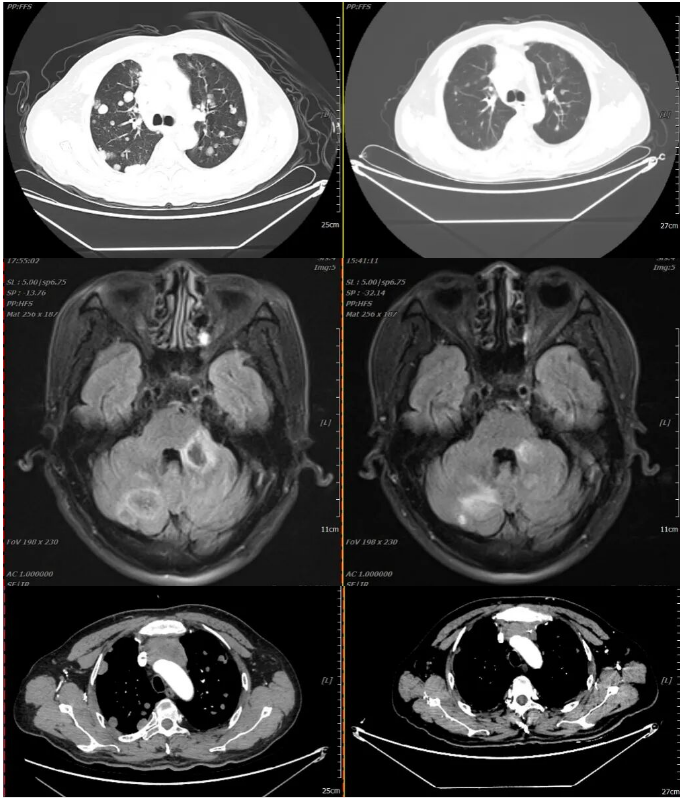

2021-02-20 2021-04-30

2周期化疗后复查疗效评价:PR

2021-04-30 2021-07-06

(四周期化疗后)复查疗效评价:SD(两肺及胸膜结节减少缩小;纵隔前间隙、纵隔内及两肺门淋巴结(2.5×3.0cm)较前部分缩小。